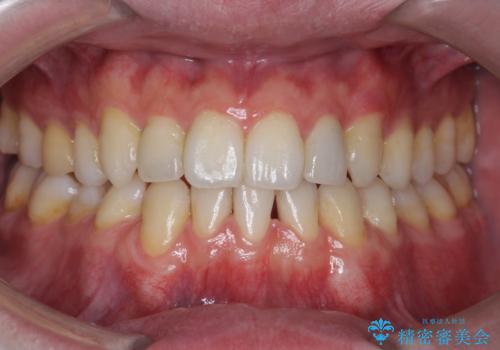

インビザラインでの臼歯の反対咬合の治療は難しいことが多いです。

今回は下の前歯を1本抜くことで、下の奥歯をしっかり内側に傾けて治療を行いました。